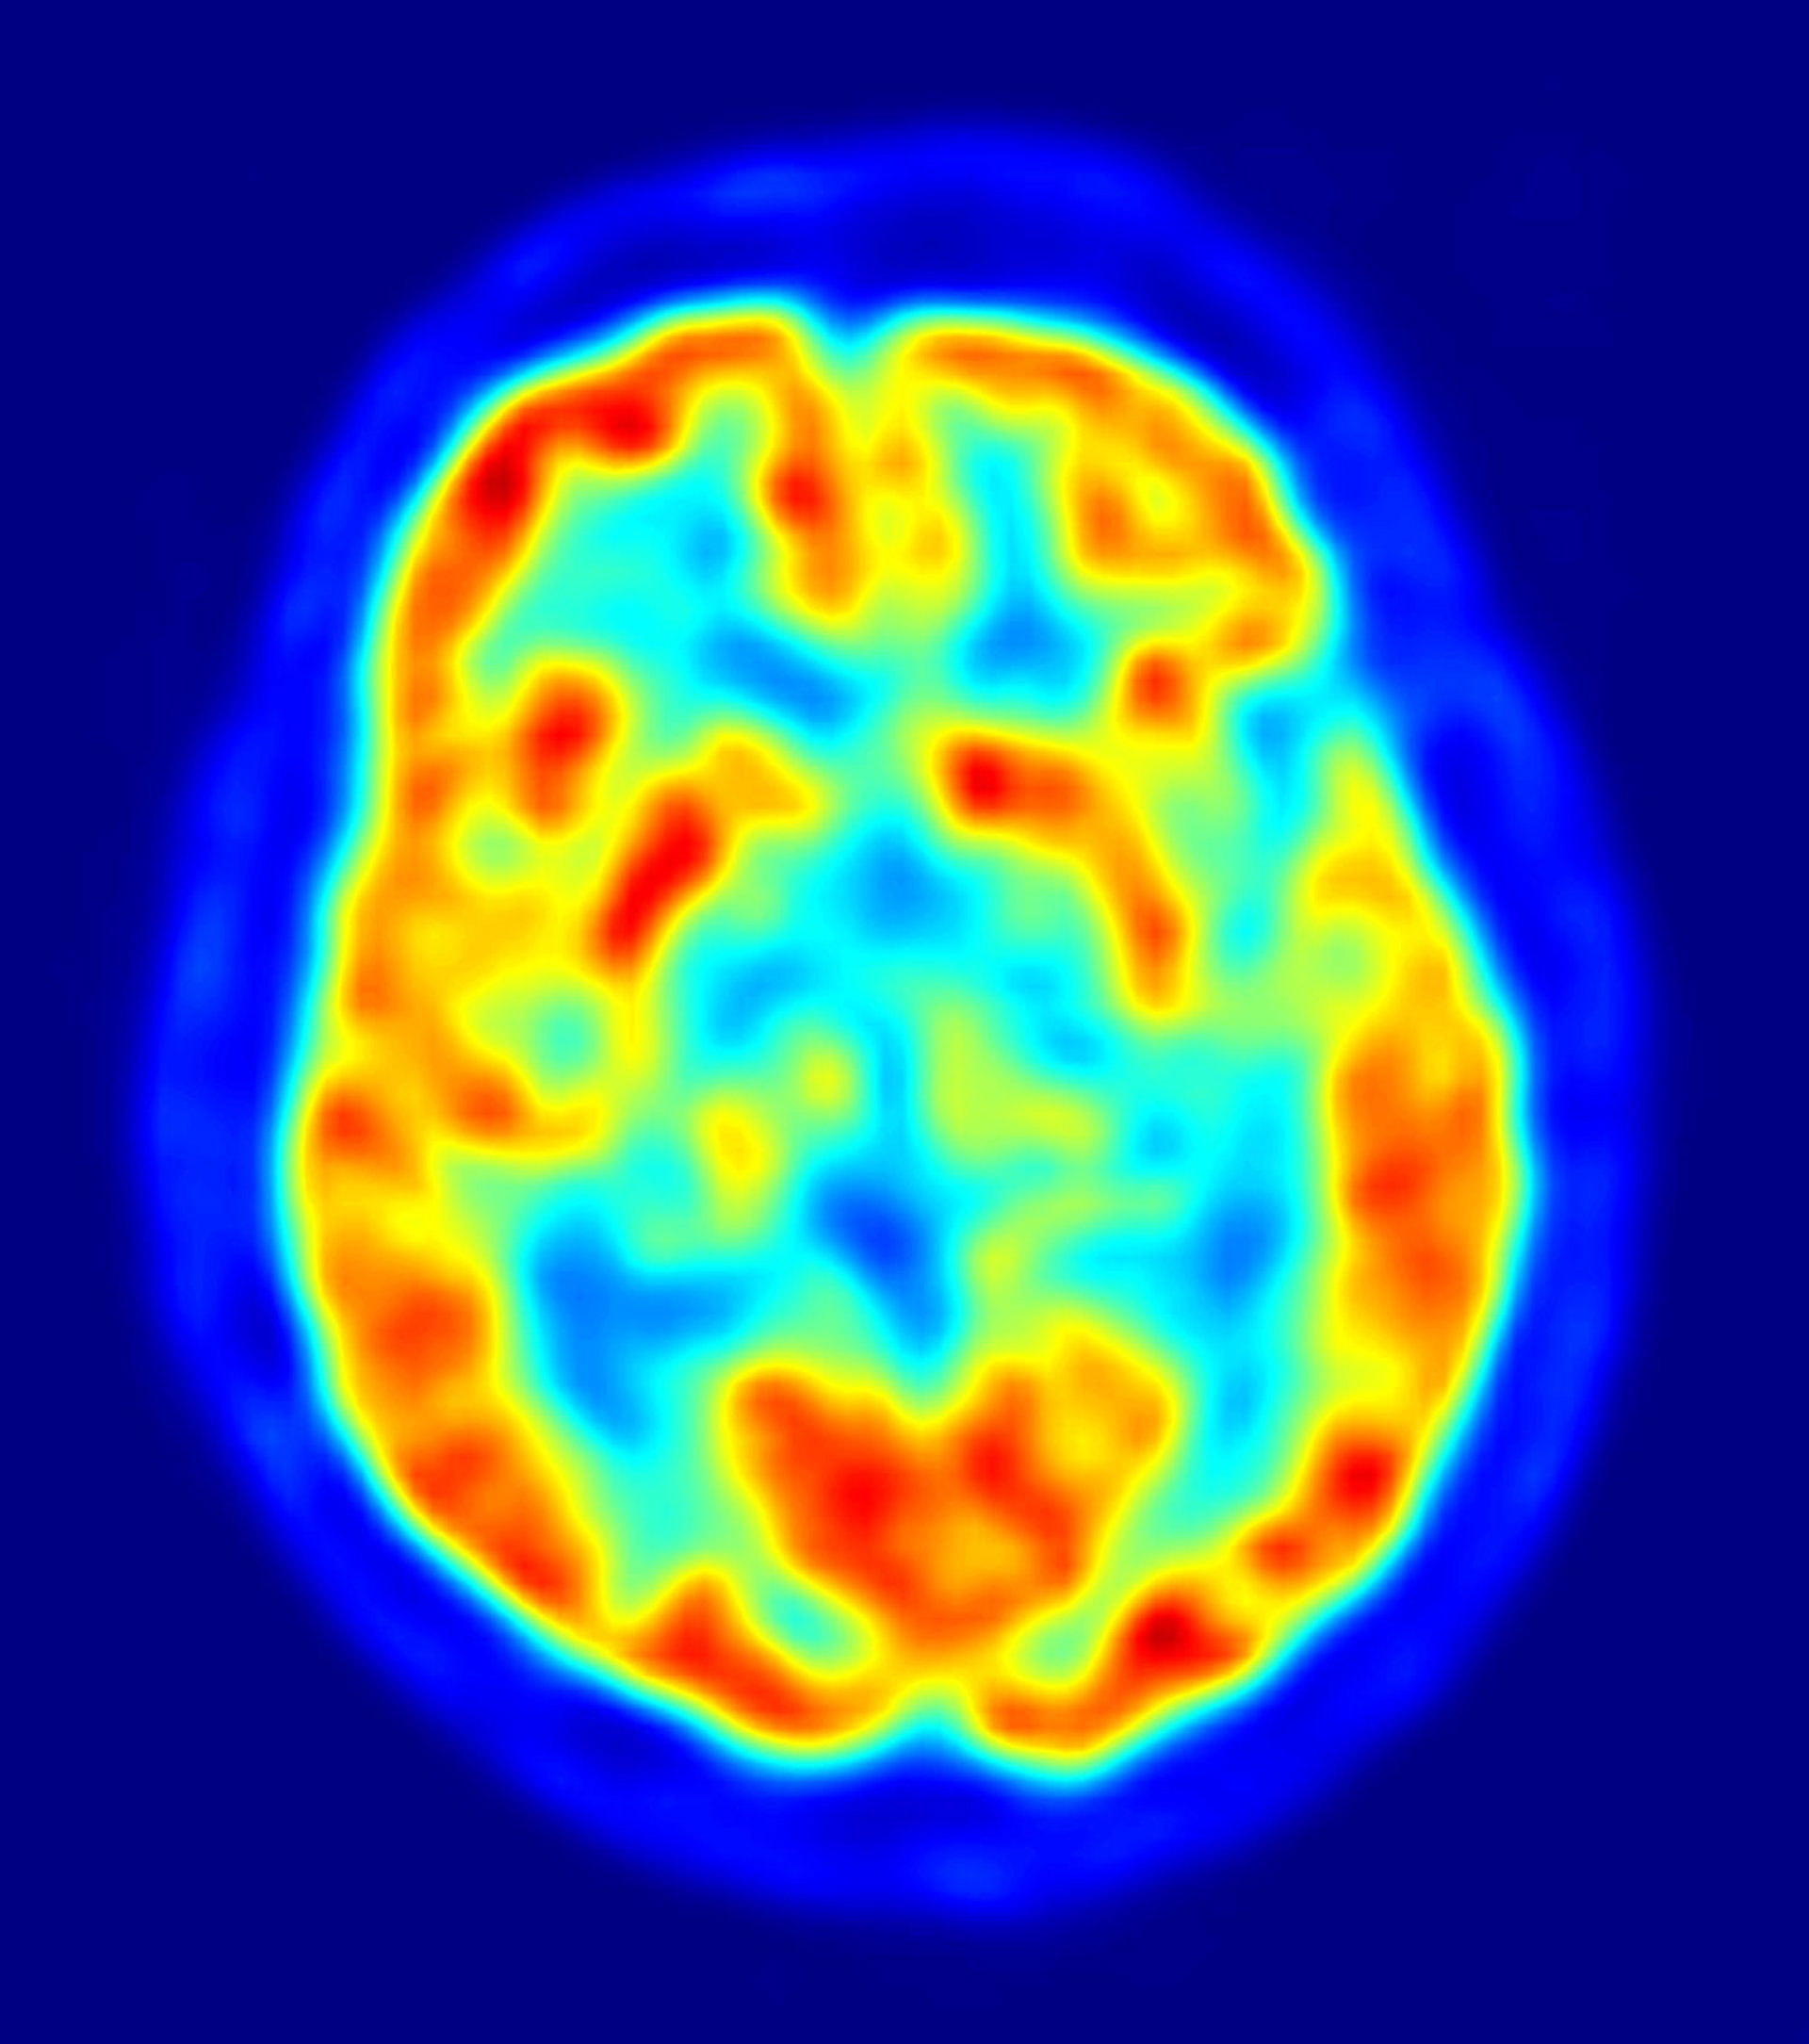

El consumo frecuente de cocaína desencadena cambios duraderos en genes que se expresan en una región del cerebro asociada con la recompensa, según un estudio de la Escuela de Medicina del Monte Sinaí en Nueva York (Estados Unidos). El trabajo se publica en la edición digital de la revista 'Proceedings of the National Academy of Sciences' (PNAS).

Los investigadores, dirigidos por Ian Maze, sugieren que estos cambios genéticos podrían influir en los cambios de conducta persistentes que se observan en los adictos a la cocaína.

Los autores examinaron marcadores genéticos, llamados marcadores de metilación de histonas o H3K9me3, que son responsables del silenciamiento de la expresión de regiones de ADN entre los genes. Los ratones expuestos de forma repetida a la cocaína expresaban menos marcadores H3K9me3 que los no expuestos y el efecto persistía incluso después de que los ratones se hubieran abstenido de la cocaína durante una semana.

Después del consumo de cocaína, sin embargo, el número de marcadores descubierto en los ratones disminuía y los autores indicaron que algunas de las regiones de ADN anteriormente silentes en el centro de recompensa del cerebro, el núcleo accumbens, se volvían activas.

Los autores subrayan que se necesitan más investigaciones para determinar si las regiones activadas de ADN influyen en el funcionamiento neural del núcleo accumbens y si causan directamente la conducta adictiva.